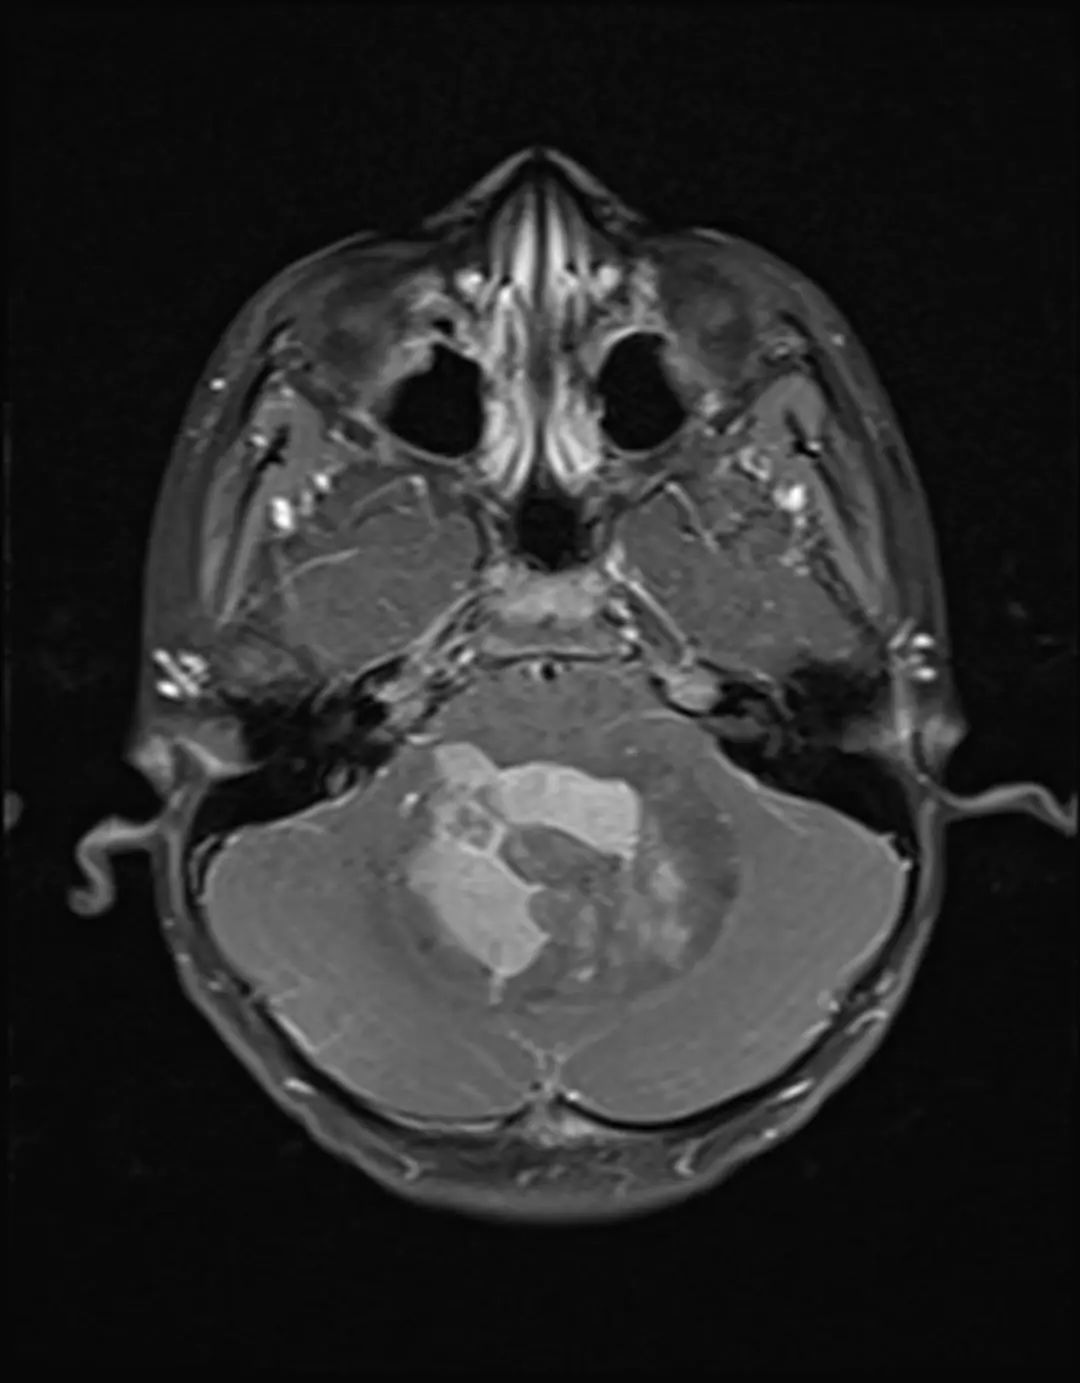

MRI表现

- T1WI:等/略低信号,T2WI上呈等/高信号。

- 边界:清晰,瘤周轻度水肿。

- 增强后:均匀强化,典型“小囊大结节”征象。

- 成人表现:MRI与CT表现均不典型。

中线小脑肿块,充满第四脑室并压迫脑干和小脑。与周围正常小脑相比,肿瘤在T1 WI上呈低信号,在T2 WI上呈轻度高信号,不均匀强化,呈囊/坏死成分,弥散受限。病理髓母细胞瘤。